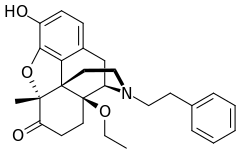

- N-Phenethyl-14-ethoxymetopon

N-Phenethyl-14-ethoxymetopon N-Phenethyl-14-ethoxymetopon |